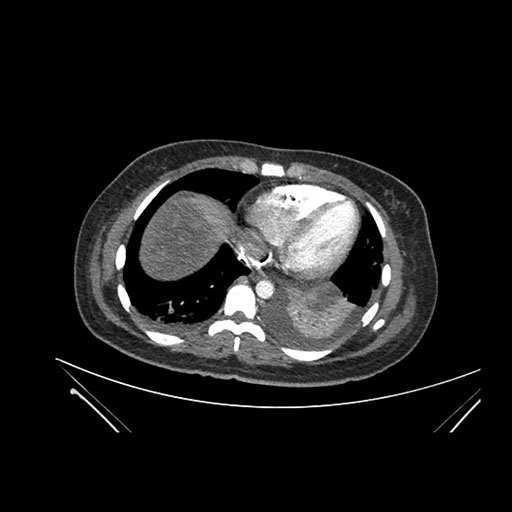

Axial Arterial

Axial Venous